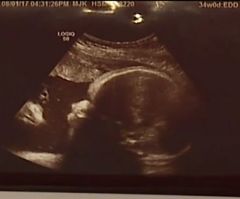

Sonogram Shows Jesus Watching Over Baby in Womb, Pennsylvania Couple Says

A Pennsylvania couple found an image of Jesus Christ watching over their unborn daughter in a sonogram.